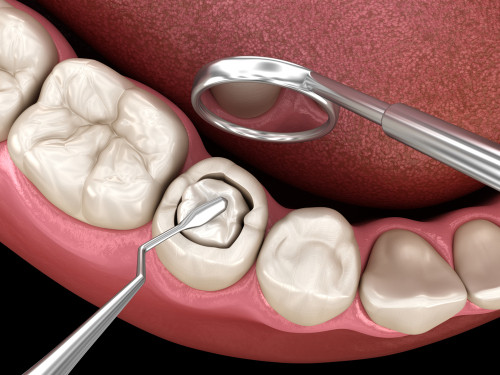

Консервативное или эндодонтическое лечение периодонтита проводится при относительно нормальном состоянии зуба и периодонта. Обычно при остром течении патологического процесса, когда изменений в тканях еще нет. Или они не столь существенны. Терапия проводится в несколько стадий:

- высверливание тканей зуба, получение доступа к пульпарной камере, а также каналам;

- удаление нервно-сосудистого пучка, т.н. депульпирование зуба с применением специальных методов и инструментов;

- обработка корневых каналов, расширение, применением антибиотиков и антисептических препаратов;

- пломбирование каналов, чтобы обеспечить их герметичность и не допустить повторного развития инфекции, современная эндодонтия предполагает использование микроскопа и специальных инструментов, чтобы не пропустить ни миллиметра;

- реставрация зуба — восстановление коронковой части.